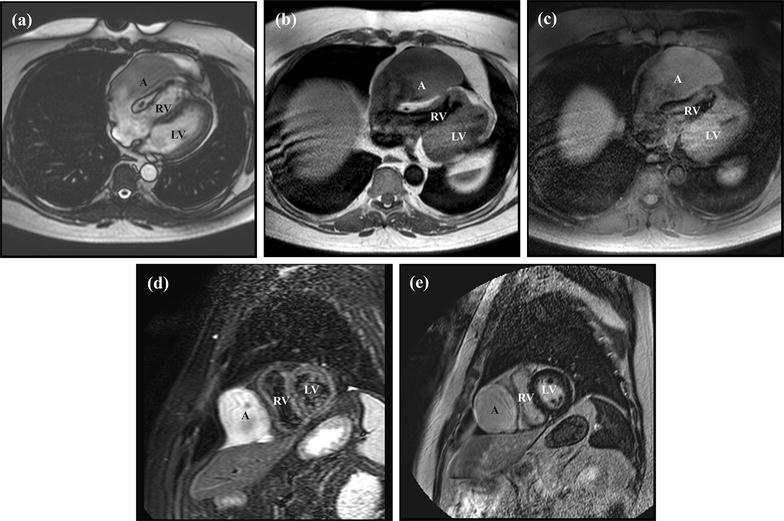

An elderly patient presented to medical attention with symptoms of acute diverticulitis. On abdominal computed tomography, a massively enlarged right atrial appendage aneurysm was discovered incidentally. The aneurysm caused marked compression of the right ventricle and contained an area of hypoenhancement concerning for an intraluminal thrombus. Gadolinium-enhanced cardiovascular magnetic resonance was performed and first-pass perfusion images demonstrated that the area of hypoenhancement was in fact poorly mixing blood. The patient was therefore managed medically.

Right atrial appendage aneurysms are infrequently encountered cardiac abnormalities. In the literature, surgery has been offered to patients who are young, symptomatic, or have evidence of thrombotic disease, although whether this practice pattern is associated with superior clinical outcomes is unclear. In the present case, gadolinium-enhanced cardiovascular magnetic resonance imaging was used to exclude the presence of intraluminal thrombus in an elderly patient, which helped orient the patient's treating team towards medical-rather than surgical-therapy.